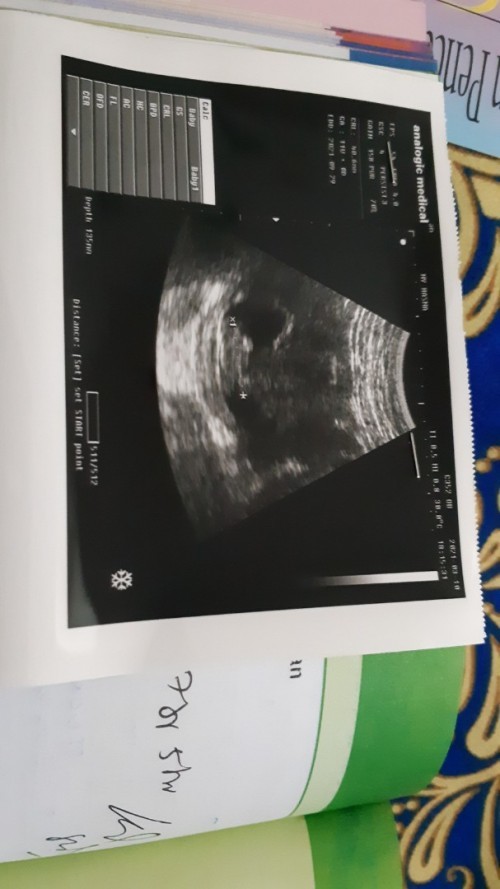

ini hasil usgku 4 week bun dah ada bakal embrio ..tpi usg t4 dr dan transvagina. .eh semalam usg t4 bidan 8week cuma ada kantong ..lngsung sedih dna kepikiran

itu kayak udh ada deh bun tapi kecil, kalo ga ada flek atau pendarahan gpp tunggu 2 minggu usg lagi aja kalo blm keliatan minta usg trans v

aku waktu usia 6 weeks udah keliatan janinnya dan udah ada DJJ nya.. tunggu dulu sampe 10weeks bun smoga pas 10weeks harusnya dh keliatan..